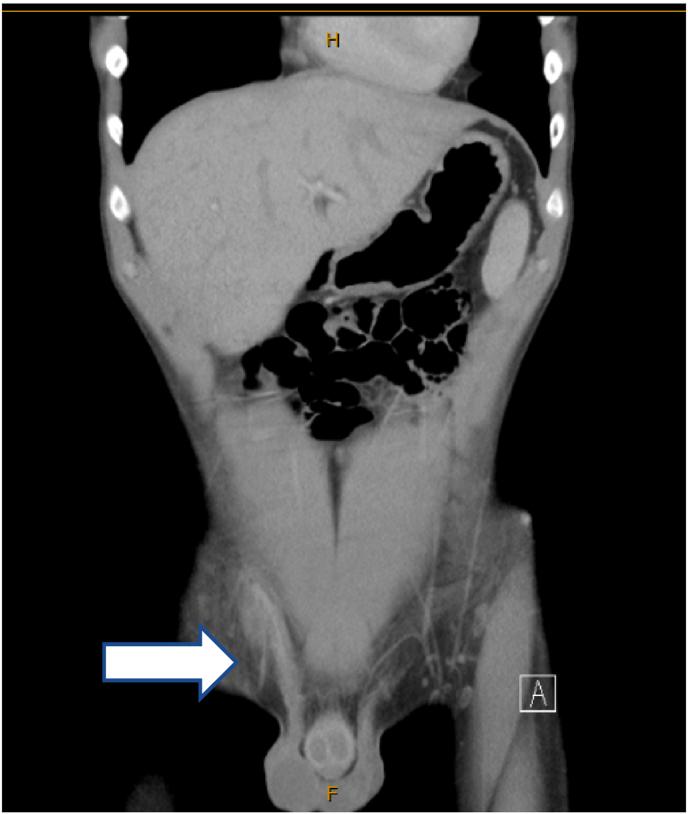

Vasitis is a rare disorder characterised by inflammation of the vas deferens. It presents with scrotal or inguinal pain/swelling, mimicking the more commonly occurring conditions such as epididymitis, orchitis, testicular torsion or an incarcerated inguinal hernia. While ultrasound may exclude some of these differential diagnoses, computed tomography (CT) or Magnetic resonance imaging (MRI) is needed to distinguish vasitis from an incarcerated inguinal hernia. Vasitis is classically treated with antibiotics so proper diagnosis is essential to avoid unnecessary surgery. We present the case of a 20-year-old male with CT diagnosed vasitis, whose condition resolved within six weeks without administering antibiotics.

输精管炎是一种罕见的疾病,其特征为输精管炎症。它表现为阴囊或腹股沟疼痛/肿胀,类似于附睾炎、睾丸炎、睾丸扭转或嵌顿性腹股沟疝等更常见的病症。虽然超声检查可能排除一些鉴别诊断,但需要计算机断层扫描(CT)或磁共振成像(MRI)来区分输精管炎和嵌顿性腹股沟疝。输精管炎的经典治疗方法是使用抗生素,因此正确诊断对于避免不必要的手术至关重要。我们报告一例20岁男性,经CT诊断为输精管炎,其病情在六周内未经抗生素治疗即得到缓解。